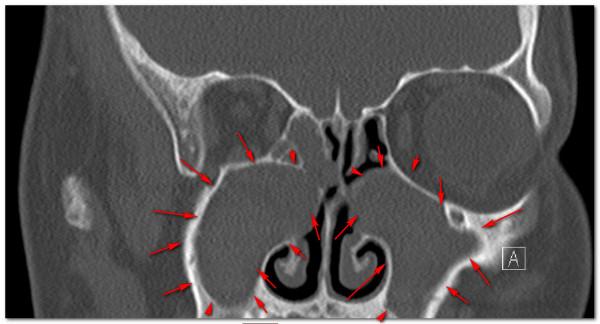

說回他的肺病,8年前當時只有9歲就患上了肺病,這種情況,要麼是先天性疾病,要麼就是幼年時患過嚴重的肺部感染落下的病根,他9歲之前病情還好,只是9歲那年患上鼻竇炎,肺部也就從此逐漸出現了咳嗽咳痰的症狀,4年的反覆發作肺功能也隨之逐漸下降,漸漸出現了氣喘、胸悶、缺氧的情況,這一次來抽動脈血測了一下,氧分壓(可以理解成氧氣含量)也達不到正常,需要吸氧了。

很多看過我科普的朋友應該知道是什麼疾病了,集齊了鼻竇炎、大量痰、呼吸阻塞、支氣管擴張、樹芽徵等這幾個要素的肺病,診斷就已經很明確了,那就是瀰漫性泛細支氣管炎,這個病首先由日本學者報道,需要長期使用大環內酯類藥物(比如紅黴素、阿奇黴素)治療,這個病如果不認識他,很有可能被長期誤診為慢性支氣管炎或者慢性阻塞性肺病,如果認識了他就好診斷了,早期診斷沒有形成支氣管擴張的話,口服阿奇黴素效果很好,甚至能治癒。